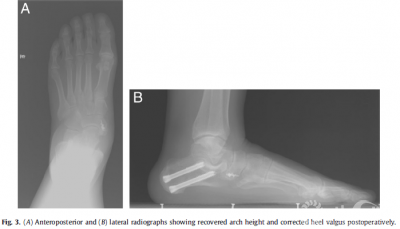

Results The16patients (21 feet)were followed up for a mean duration of 28.5 months (range18 to 48). All patients were satisfied with their clinical results andwere abletowalk long distanceswithout any pain 6 months after surgery. No cases of woundinfection or nerve injury developed.The mean AOFAS ankle and hindfoot scoreshad improved from 53.3±6.5preoperatively to 90.8±1.4 at the last postoperativeassessment(p<.01; Table 1). The improvement in all radiographic parameters wasstatistically significant between the preoperative and last follow·up assessments(p < .01; Table 2). These changes provided evidence of recovery of the archheight and correction of heel valgus (Fig. 3). The foot appearance alsosuggested satisfactory outcomes (Fig. 4).

Heel valgus has been shownto be corrected well using MDCO, with restoration of the gastrosoleal complexas a heel invertor, which increases the supinatory ground reactive forces anddecreases the medial arch load. In our study, flatfoot and heel valgus alignmentwere corrected in all 16 patients. The average longitudinal arch heightincreased from 21.9±1.4 mm to 30.8±1.9 mm, with accompanying improvements in the mean AOFAS ankle andmidfoot scores. All patients were satisfied with their clinical results, andthe procedure was accomplished without complications or infection.Thesatisfactory clinical outcomes in the present study warrant the initiation oflarger studies with longer follow·up to further validate the procedure. Webelieve that the results of our investigation could be useful in thedevelopment of future studies focusing on the surgical correction of the pesvalgus flatfoot deformity.